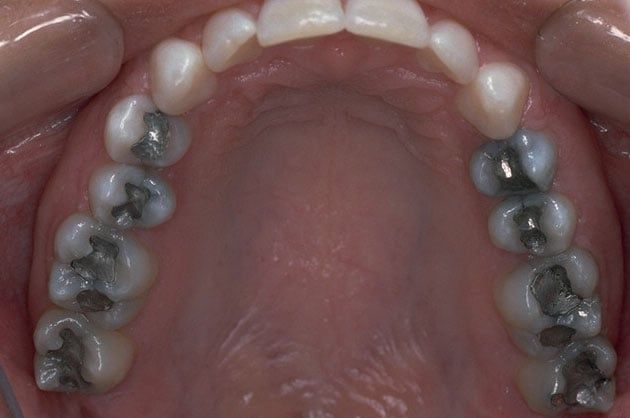

Replacing Old Fillings

There is now new technology that allows you to replace old silver and gold fillings with a more natural looking, composite filling. Composite fillings are bonded to the tooth and research has proven them to be about 90% as strong and healthy as natural tooth material.

Old fillings have been known to break down overtime, creating the potential for cavities, pain or even cracking the tooth itself! Composite fillings can be completed in a single visit, look and function like your natural teeth and have less of a chance of problems in the future.

Virtually everyone is a candidate to have metal fillings replaced with natural-looking white fillings. Request an appointment online or call our office directly at (707) 557-5822 to discuss replacing your old metal fillings with white ones.